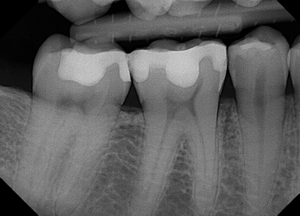

An example of a bad X-ray image

An example of a good X-ray image